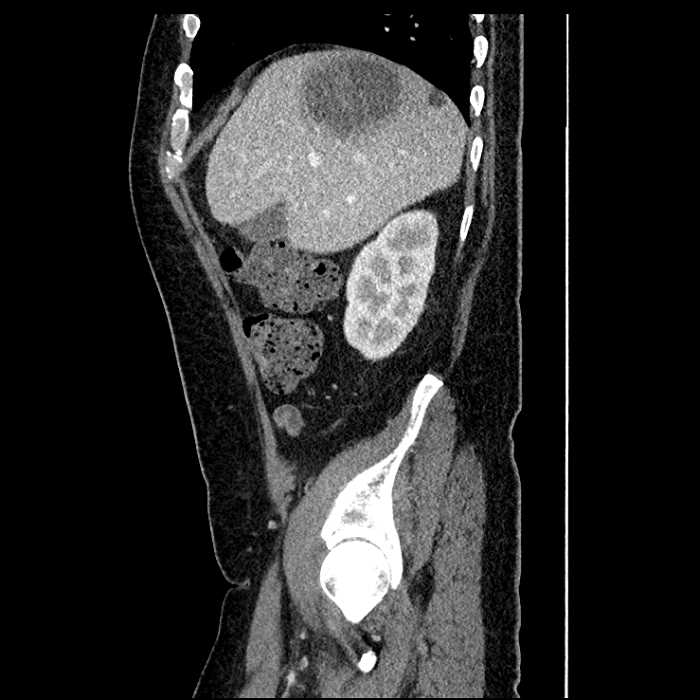

Age: 63

Sex: Male

Indication: Abdominal pain

• Large fluid density structure in hepatic segments 7 and 8 measuring 10 x 7 x 7 cm with internal septation and circumferential ill-defined low density compatible with edema

• Peripherally enhancing subcapsular collections along the anterior margin of the left hepatic lobe measuring 3 x 1 cm and 2 x 1 cm

• Clearly marginated fluid density structure in segment 7 and several other scattered tiny hypodensities, which likely represent cysts

• Mild mural thickening of a segment of the sigmoid colon with adjacent fat stranding and a 1.5 cm fluid and gas collection along the tip of an inflamed diverticulum

• Loss of the normal fat plane between this collection and adjacent loops of small bowel, which demonstrate mural thickening

• Hepatic abscess

Acute sigmoid diverticulitis complicated by a small contained perforation and a large abscess in the right hepatic lobe. Additional small subcapsular abscesses along the anterior margin of the left hepatic lobe.

Additionally, loss of the normal fat plane between the peridiverticular collection and adjacent thickened loops of small bowel raises the potential for an enterocolonic fistula.

• The classic CT imaging appearance is a double target sign with internal low density surrounded by an internal enhancing rim (capsule) and a low density external rim (edema)

Hepatic abscess showing the double target sign with low density internally surrounded by a thin inner enhancing rim (red arrow) and ill-defined outer low density rim (yellow arrow). Blue arrow indicates an internal septation. Red arrows: additional smaller subcapsular abscesses. Red arrow: focal contained perforation associated with diverticulitis.